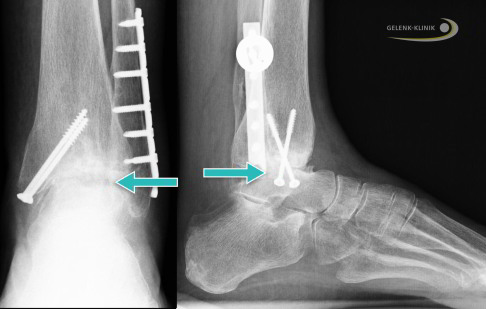

Operative Prävention der Talusnekrose nach Talusfraktur

Die Nekrose des Talus ist häufig Folge und Komplikation eines Knochenbruchs. Je nach Art der Talusfraktur liegt die Nekroserate zwischen 10% und 100 %. In 75 % der Fälle tritt nach einer Nekrose oder Fraktur eine Arthrose auf. Eine Verhinderung der Nekrose ist also wichtig, um die Gelenke des Talus zu retten. Bei Frakturen des Talus liegt die größte Chance zur Prävention der Talusnekrose oder des Sprungbeintodes in einer raschen Versorgung des gebrochenen Sprungbeins. Innerhalb der ersten 6 Stunden nach dem Unfall stehen die Chancen für eine komplikationsfreie Versorgung der Talusfraktur am besten. Hier kann die schonende Operation wichtig sein, um eine Talusnekrose zu vermeiden. Bei dieser Methode bringt der Operateur die Bruchfragmente des Talus wieder in die korrekte Position.

Kommt es durch die Schwächung der Tragfähigkeit und Stabilität des Knochens zu einem Zusammenbrechen (Kollaps) des nekrotischen Talus, ist eine Stabilisierung in einer guten Stellung mit Versteifung unter Einsatz von Ersatzknochen und Knochenspänen hilfreich und unumgänglich. Dies verhindert schwere Deformitäten des Fußes und eine Störung der Bewegungsabläufe beim Abrollen des Fußes.